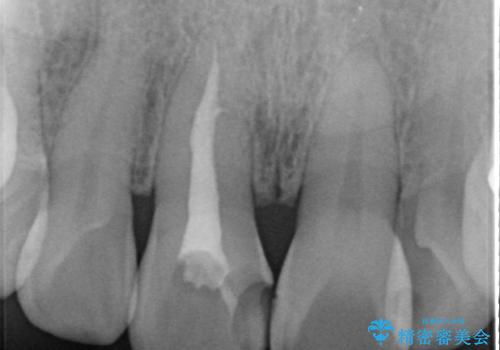

- 前歯の変色の改善を希望され来院されました.

以前に神経が死に、根管治療を行った歯の変色が認められたためセラミックによる審美補綴治療を計画します。

神経の死んでいる歯について

神経治療を行い補綴(かぶせもの)治療を行わないと、変色が目立ち審美障害を起こすことがあります。